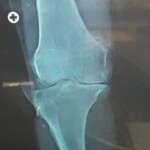

Computerised Knee Replacement

Use of computer during  knee replacement make it possible to place implant or prosthesis in perfect position and correct alignment which increase long term survival of implant or prosthesis and better function outcome.